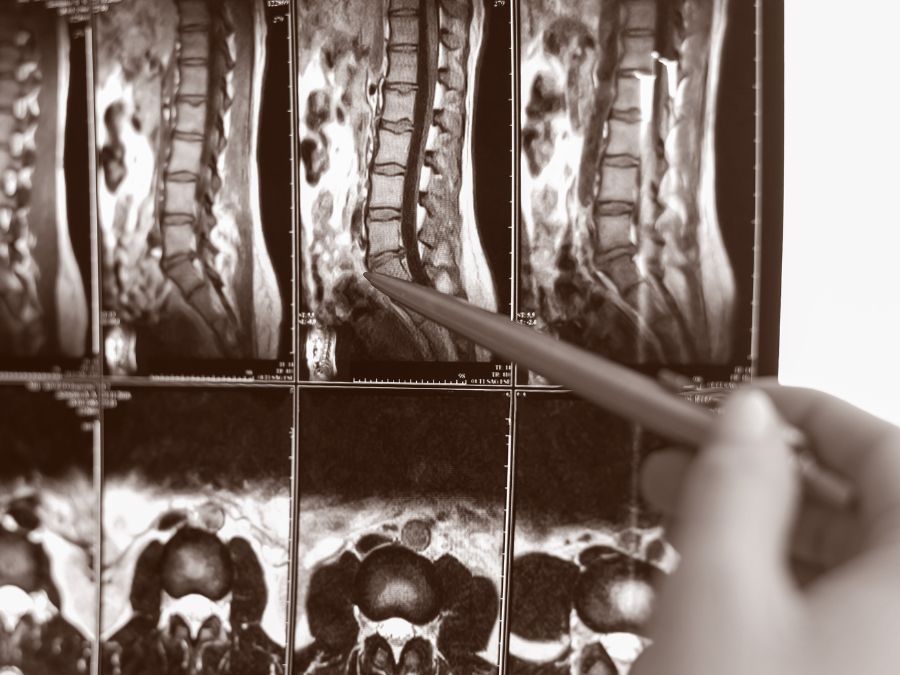

Presso la clinica O3 siamo in grado di offrire una tecnica innovativa, estremamente precisa: l’ozonoterapia RX guidata. Questa procedura prevede l’infiltrazione della miscela di ossigeno e ozono sotto guida radiologica, grazie all’utilizzo di un amplificatore di brillanza o di una TAC.

Esecuzione di ozonoterapia RX guidata alla colonna vertebrale sotto guida radiologica.

Infiltrazione di ozono alla colonna vertebrale sotto guida TAC o amplificatore di brillanza presso un centro specializzato.